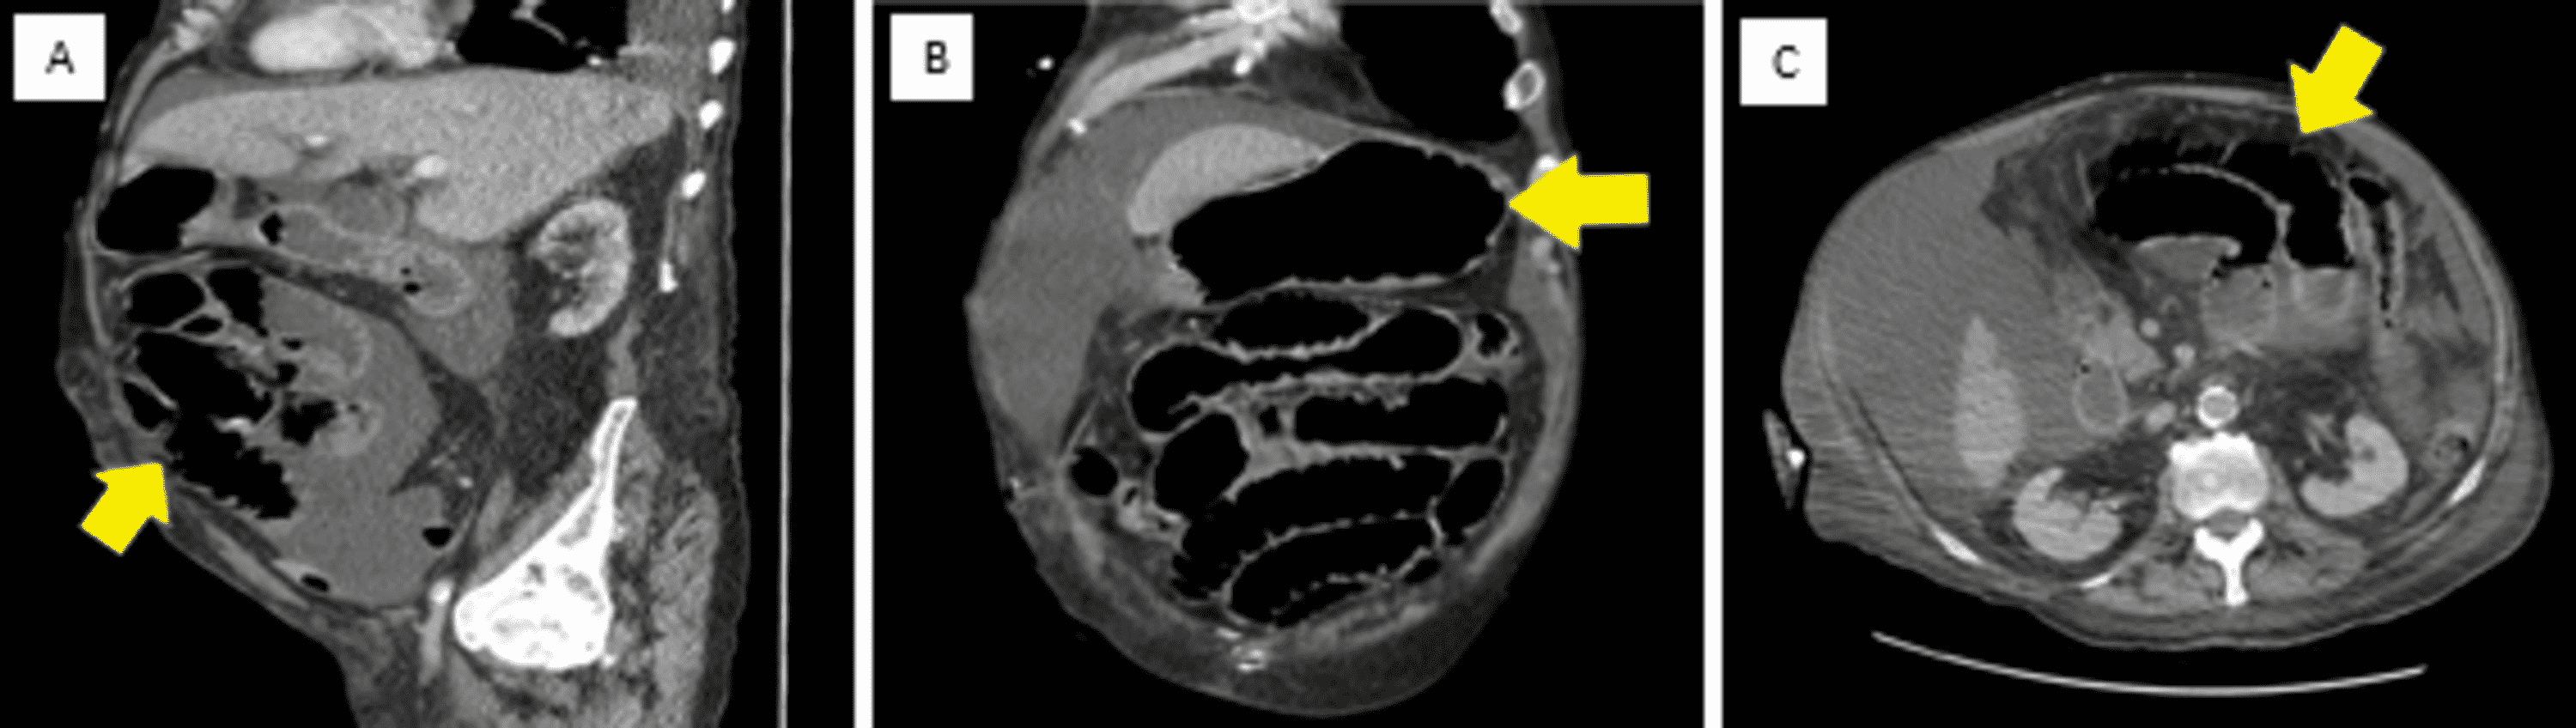

Check out now the facts you probably did not know about. We report the case of gallstone ileus in a 94-year-old Caucasian female who presented to the. Coffee ground emesis dark brown and granular blood altered by stomach acids suggests a slowed or stopped gastric or duodenal bleed.

Furthermore there were episodes of. Possible causes include Gastrointestinal Hemorrhage. Although patients were admitted for UGI bleeding the more significant associated diagnoses included acute myocardial infarction urosepsis small bowel obstruction bilateral pulmonary emboli and acute renal failure.